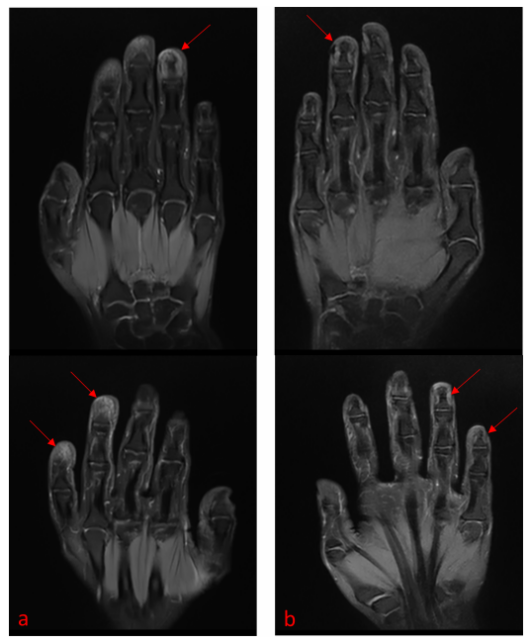

左无名指、右无名指及右小指远端指骨内可见斑片状T2/短时间反转恢复序列(STIR)高信号、T1低信号(图2a),符合活动性骨髓水肿表现。

图2 赛立奇单抗治疗前基线及治疗后的MRI表现

注:治疗后冠状位T2加权脂肪抑制序列显示,患者左第四指、右第四指及右第五指远端指骨的骨髓水肿得到显著改善,且部分消退。

第20周,甲周炎症完全消退,新生光滑甲板仅见轻度纵向嵴状突起,手指肿胀、压痛症状亦完全消失(图1b)。DLQI评分改善至2/30,VAS疼痛评分降至0/10。MRI随访检查显示,原受累远端指骨部位T2/STIR高信号显著减低(图 2b),提示骨髓水肿明显消退,软组织肿胀近乎完全缓解。

影像学证据:从皮肤到骨骼的深度调控

ACH常伴随骨组织改变,其机制可能与炎症介质向邻近骨组织蔓延有关,以及局部神经血管功能损害加重骨髓水肿。值得注意的是,即便采用先进的经皮给药系统,外用药物也难以在真皮层以外达到有效药物浓度,因此对骨髓水肿等深部炎症的治疗效果有限。本病例中,基线MRI检查显示患者远端指骨存在明显骨髓水肿,符合炎症性骨炎表现;经甲周注射赛立奇单抗后,骨髓水肿显著消退,提示局部高浓度阻断IL-17信号通路能够调控从皮肤蔓延至骨组织的深部炎症活动。

最后,ACH的骨组织受累是临床处理难点。研究表明,约20%-40%的ACH患者可并发关节炎,骨侵蚀是远期风险。本病例中,基线MRI显示的骨髓水肿在治疗后显著消退,这是首次以影像学手段证实局部IL-17A阻断能够调控从皮肤延伸至骨骼的深部炎症。这一发现拓展了临床对ACH病理过程的理解,也为评估治疗深度提供了新的视角。